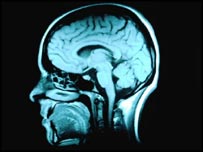

اسکن مغز

بخش های مشخصی از مغز در هنگام تفکر در باره آینده فعال می شوند